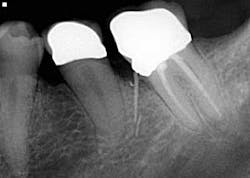

• Missed canals

Know your tooth anatomy and the possible variations of the canals (figure 2). The molars present with the most diverse canal composition—“additional canals in the mesial roots of maxillary molars and the distal roots of mandibular molars are the most frequently missed” (2)—but even the premolars and incisors can prove to be a formidable foe. Remember the article by David Landwehr, DDS, MS, titled “The myth of ‘easy’ root canals in endodontics”? Read it if you haven’t. Lastly, don’t skimp on your occlusal access and use magnification.